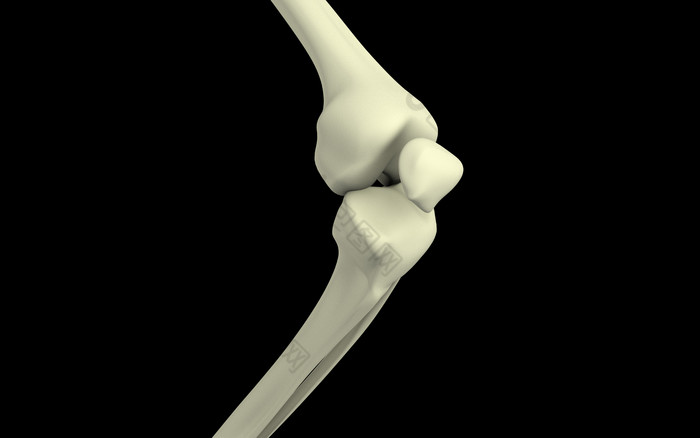

人体膝盖弯曲骨骼结构插图

图片尺寸700x438